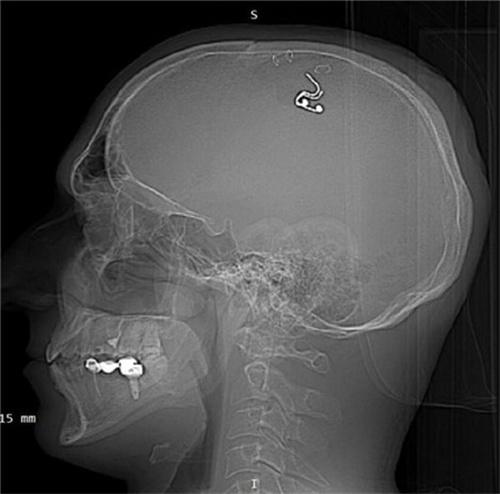

7月23日以及俄羅斯男子為控制夢境在大腦內植入芯片的話題,充上了微博的熱搜,不少網友也對于這一舉動感覺到不可相信。俄羅斯40歲的一名男子邁克爾-拉住加,此前一直在鉆研神經科學等這些領域,近日邁克爾-拉杜加在家中自己做腦部的手術,僅僅進行了半個小時,就失血達到了一升多,仍然將電極成功植入到大腦當中。最后經過設備的觀測,不同睡眠狀態(tài)之下有三次夢境情節(jié)發(fā)生改變的情況出現,也出于對健康的考慮,五周后還是前往醫(yī)院將腦中植入的電極移除了